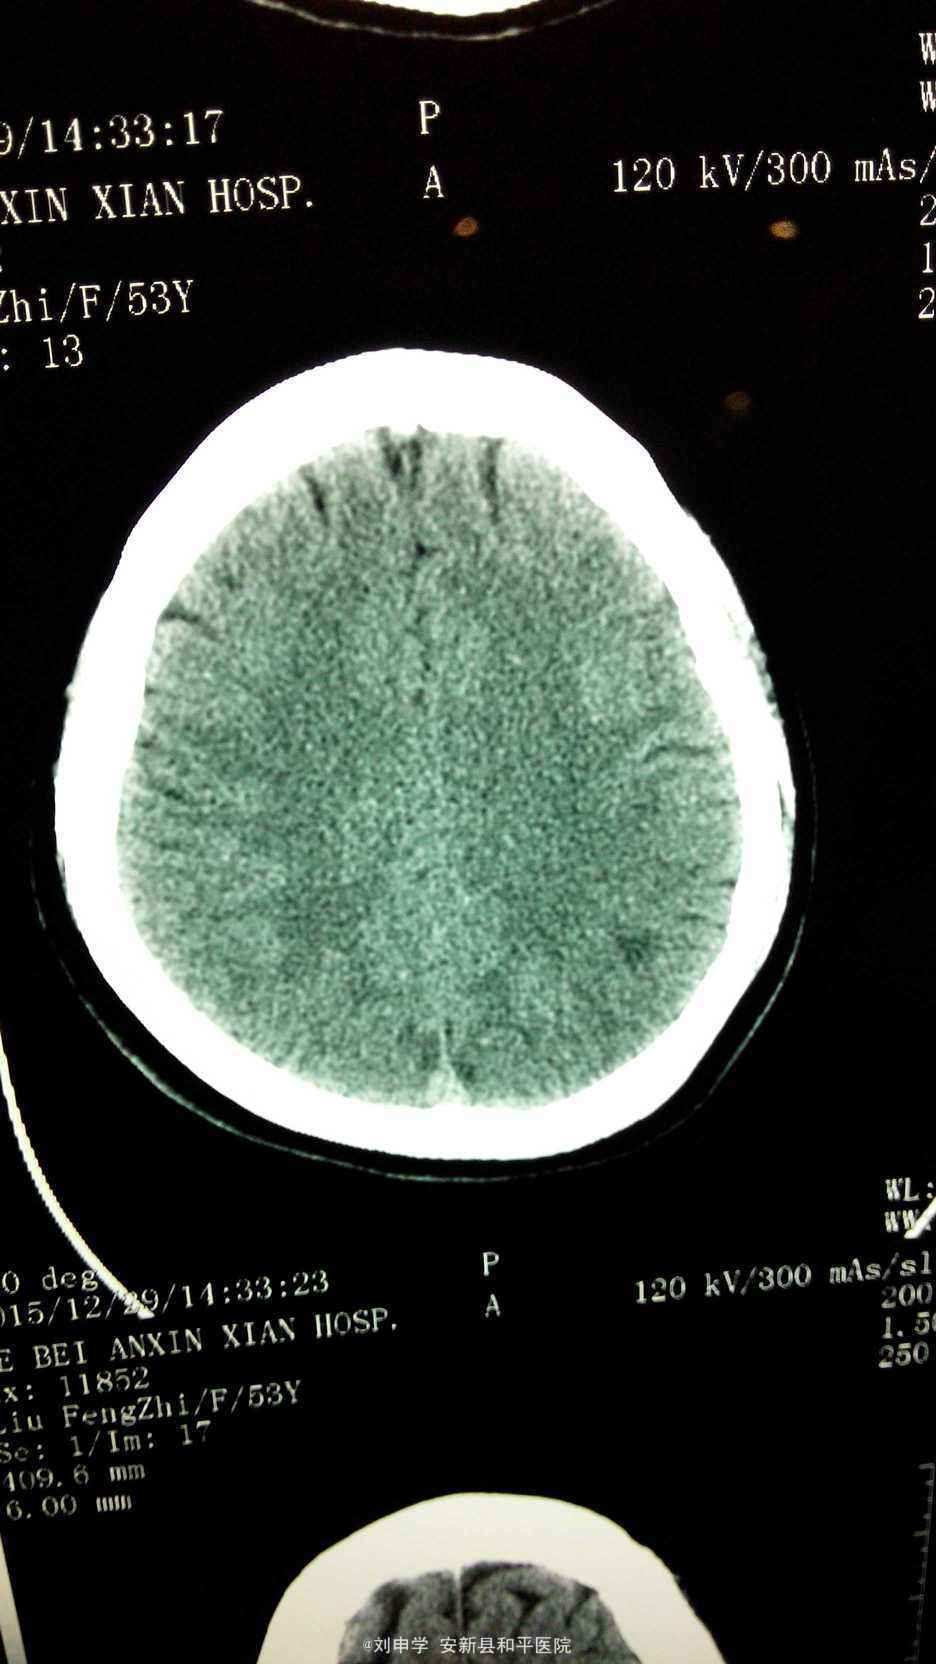

查体血压160/100mmHg, 神清,双侧瞳孔等大正园,对光反射正常,无偏盲,复视。心率56次./分,四肢肌力,肌张力正常,双巴氏征阴性。心电图:窦律心率56次/分。头颅CT提示左额叶顶叶脑梗塞。化验血脂正常。

入院初步诊断:1.脑梗塞,2.高血压。给予抗血小板,活血及营养脑细胞,调脂,降压等治疗。住院10天好转出院。